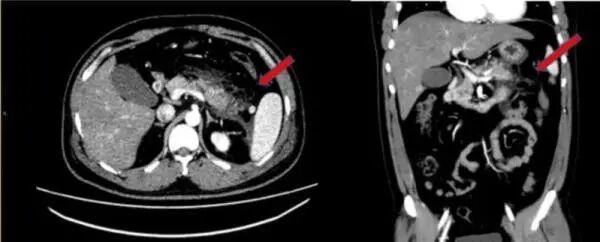

腹部增强CT提示胰腺尾部肿胀,胰腺周围脂肪间隙模糊,多发斑片状。

血压检验更是标注多项指标异常,甘油三脂高达44.49毫摩尔/升,是正常人近25倍,胆固醇是正常人的近3倍。

医生检查后断定,男子所患的是急性坏死性胰腺炎和2型糖尿病伴酮症酸中毒。